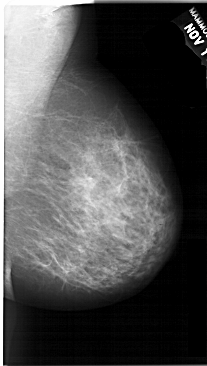

A_1691_1.LEFT_CC

LEFT_CC LINES 6871 PIXELS_PER_LINE 3946 BITS_PER_PIXEL 12 RESOLUTION 43.5 OVERLAY